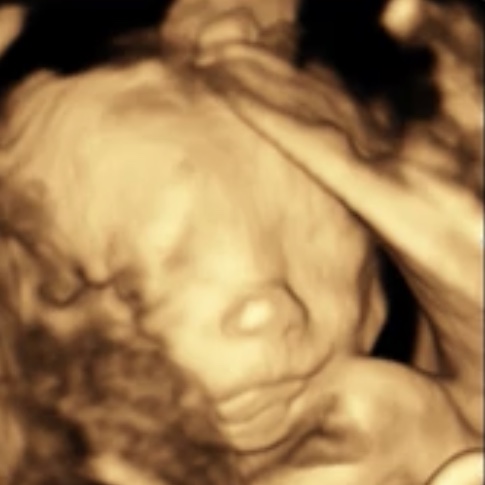

Помню как писала тут на 5 недельке , а сегодня 23 началась, есть девочки односрочницы тут ? У меня пдр на 18 февраля ставят, мы уже вот такие большие, на папу похожи )))

У меня 13 февраля пдр , а на фото что это?

К меня пдр 22 февраля по календарю) врач про пдр не говорит ничего пока)), но тоже так же, наверное) Вторая фотка хорошая, тьфу тьфу растите и развивайтесь хорошо) моя на 3д узи закрывала ручками глазки)